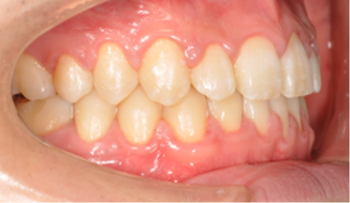

​​​​​​​Case 01. 덧니 & 치열 불규칙

덧니가 있거나 치열이 불규칙한 경우, 심미적으로도 보기에 좋지 않지만, 기능적으로도 본연의 역할을 상실하게 됩니다.

이 경우 교정 치료 방법은 크게 치아를 빼고 하는 방법과 치아를 빼지 않고 교정하는 방법으로 나뉩니다.

교정 치료 Before & After

• 덧니 & 치열 불규칙 교정 치료 후

After